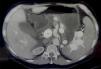

An abdominal and pelvic contrast-enhanced computed tomography scan showed arterialization of the portal vasculature with normal liver parenchyma, moderate ascites, and splenomegaly, ruling out other causes of portal hypertension and ascites (Fig. 1). Further imaging revealed communication between the splenic artery and vein. Angiography confirmed a SAVF, which was treated with coil embolization via the femoral artery approach with a 6 F sheath; the splenic artery was cannulated with a 5 F Cobra C2 catheter. Digital subtraction angiography (DSA) revealed an aneurysmal dilation of the splenic vein, without opacification of the splenic parenchyma (Fig. 2). The fistula was successfully embolized using coils placed via a microcatheter (Fig. 3). Post-procedure, the patient’s ascites and esophageal varices improved, and one year later, she does not need beta-blockers or diuretics and shows no signs of clinically significant portal hypertension.